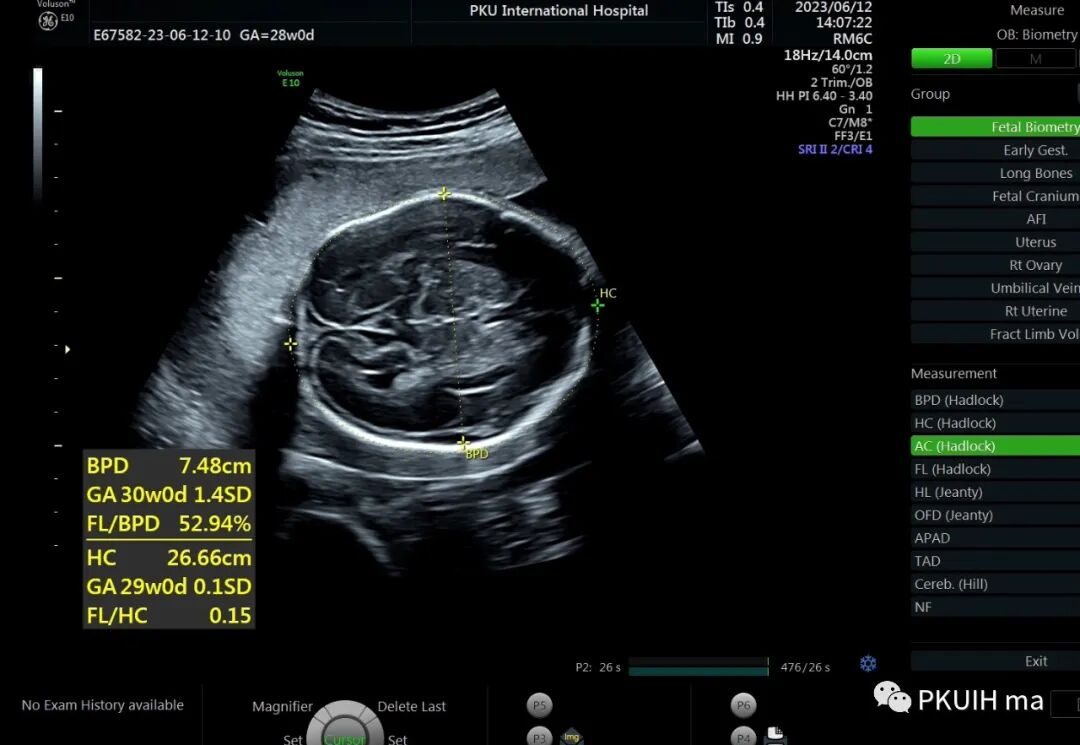

28周检查发现肢体越来越短

头围双顶径大于28周,骨骼回声强度未见明显异常